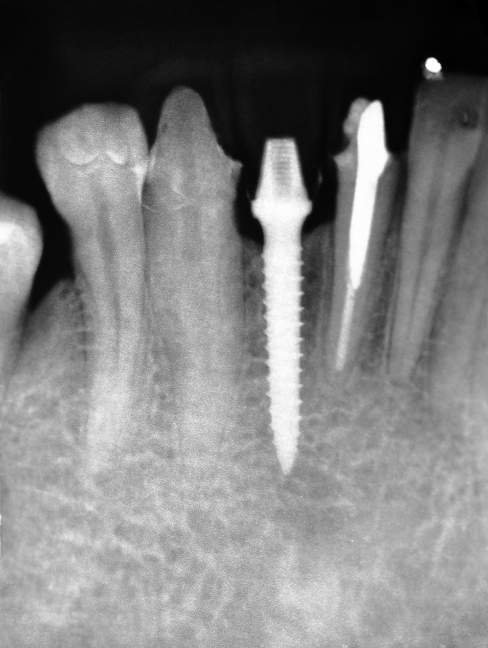

Implantes estreitos de titânio surgiram na Implantodontia com a indicação clássica de serem utilizados para substituição de incisivos laterais superiores, incisivos inferiores (Fig.1), espaços edêntulos pequenos e com baixa incidência de carga mastigatória.

O implante Slim Pilar de corpo único com os diâmetros de 2,5 e 3,0 milímetros (Fig. 2) foram desenvolvidos para superar o desafio de pequenos espaços desdentados.

Como o implante perde pouco osso proximal quando posicionado na altura da crista óssea, o implante pode ser colocado tão próximo quanto 1 mm a raiz do dente adjacente.2 Portanto, o espaço mesio-distal um implante de 3,0mm de diâmetro, por exemplo, pode ser tão pequeno como 5,0mm. As principais indicações para os implantes dessas dimensões são:

CASO CLÍNICO

Paciente com perda do incisivo central inferior do lado direito, utilizando uma prótese fixa em zircônia com estética e adaptação deficientes.